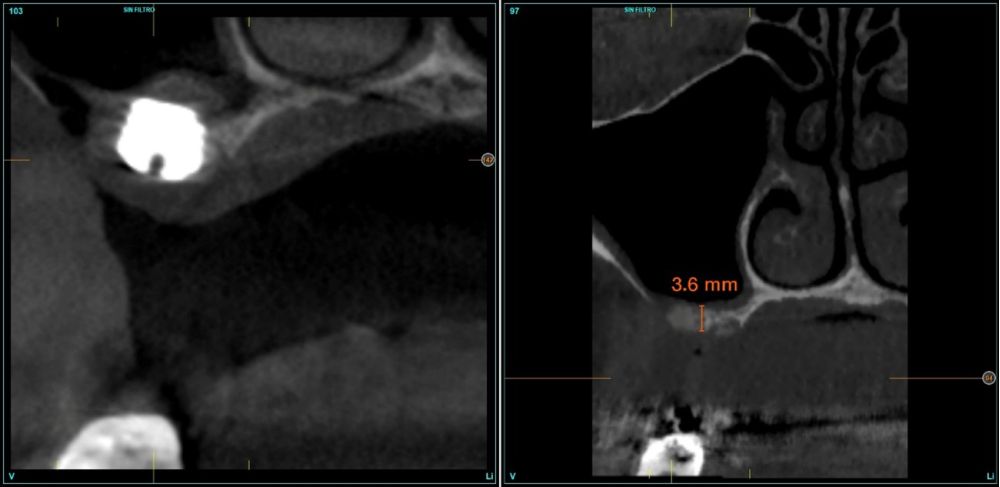

Fueron reclutados de forma retrospectiva pacientes en los que se llevase a cabo una inserción de implantes dentales de 4,5 mm de longitud en crestas óseas residuales de hasta 4,5 mm de altura con elevación de seno transcrestal, utilizando como material de injerto hueso autólogo obtenido del fresado y PRGF-Endoret, unido a la inserción directa con anclaje en la cortical desde junio de 2020 hasta septiembre de 2021. Antes de la colocación de los implantes, todos los pacientes fueron evaluados mediante modelos diagnósticos, exploración intraoral y un CBCT (Cone Beam Computed Tomography), cuyo análisis se realizó con un software especializado (BTI-Scan III), para conocer la altura exacta de la cresta ósea residual y la densidad, y poder adaptar en consecuencia el protocolo y el implante a colocar. Como protocolo preoperatorio, se administró una premedicación antibiótica con amoxicilina (2 g por vía oral) una hora antes del procedimiento, junto con paracetamol (1 g por vía oral) como analgésico. Tras la intervención, los pacientes continuaron con un tratamiento antibiótico de amoxicilina (500-750 mg por vía oral cada 8 horas, según el peso) durante cinco días. La colocación de los implantes fue realizada por un mismo cirujano utilizando la técnica de fresado biológico, caracterizada por bajas revoluciones y ausencia de irrigación, ajustando el procedimiento a la densidad y volumen del lecho óseo receptor para asegurar una adecuada estabilidad primaria del implante8-9.

El acceso final a la cortical sinusal se efectuó con una fresa específicamente diseñada para esta técnica (fresa de corte frontal), la cual permite la eliminación controlada del suelo del seno maxilar sin comprometer la integridad de la membrana de Schneider10. Una vez expuesta la membrana a través de la perforación en la cresta ósea, se realizó su elevación de manera controlada, colocándose el injerto consistente en hueso autólogo obtenido del fresado de otras localizaciones en las que se colocan implantes en el mismo acto quirúrgico embebido en PRGF-Endoret. Por último, la colocación del implante se llevó a cabo con un motor quirúrgico calibrado a 25 Ncm y 25 rpm, mientras que la inserción final se realizó manualmente mediante una llave dinamométrica para asegurar una fijación óptima (Figura 1).

En todos los casos se realizaron elevaciones óseas desde los 0,2 hasta los 1,3 mm. En la Figura 2 se observa la altura ósea inicial y final para cada uno de los implantes. Las posiciones más frecuentes de los implantes incluidos en el estudio fueron en 16 y en 26 con 33,3% respectivamente, y la menos frecuente en posición 27 (11,1%). Todas las posiciones se muestran en la Figura 3.